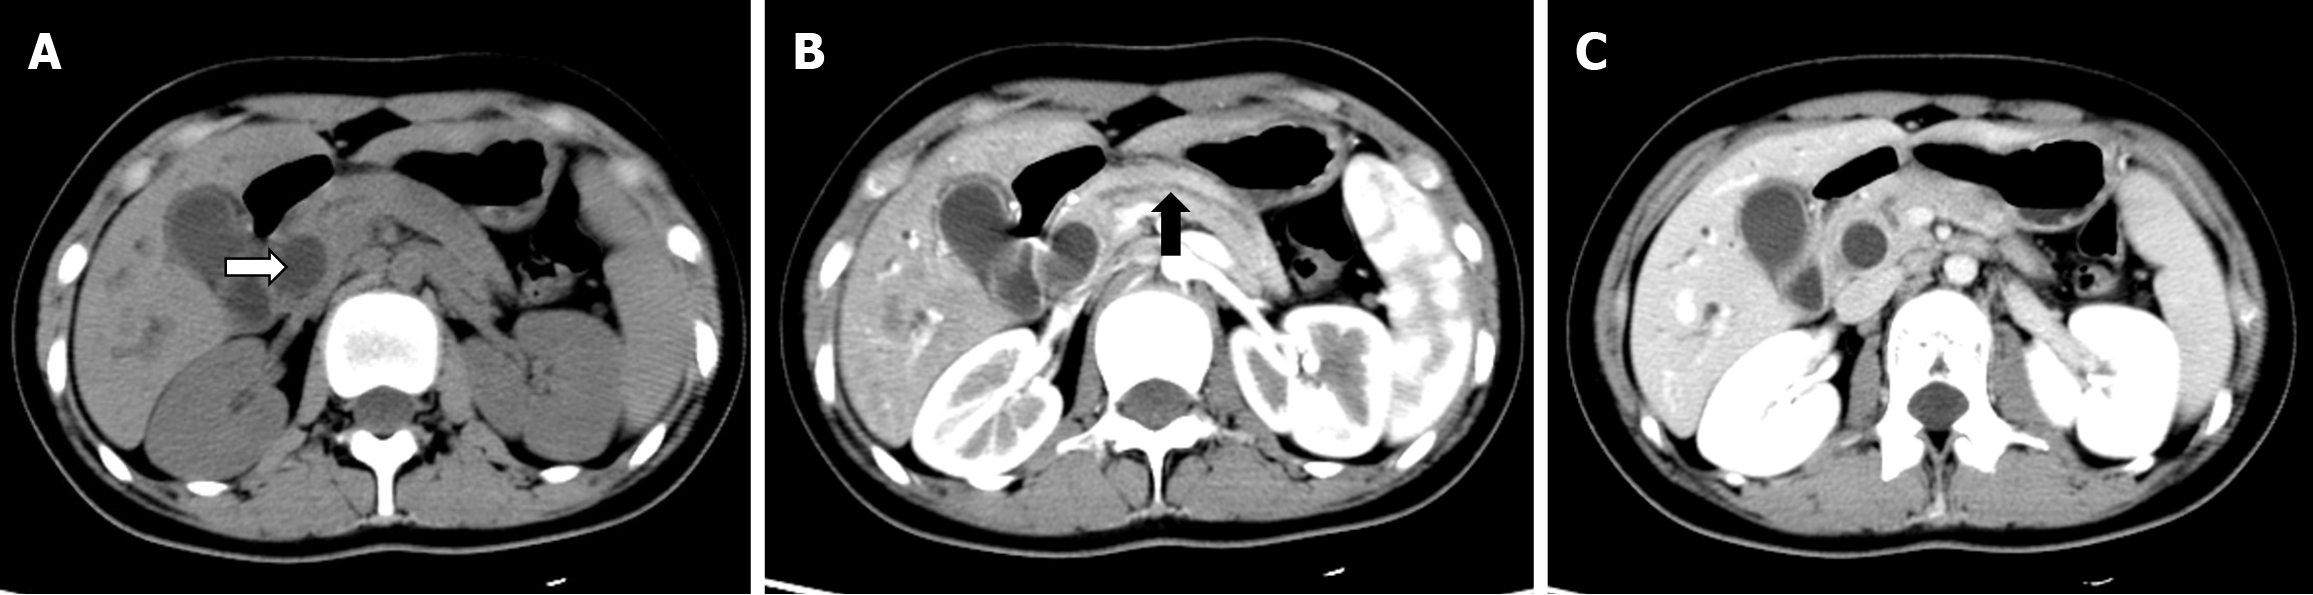

Plain and enhanced upper abdominal computed tomography performed on August 17, 2023, demonstrated an enlarged gallbladder, a dilated CBD with a maximum diameter of approximately 1.3 cm, and a slightly dilated main pancreatic duct (Figure 3).